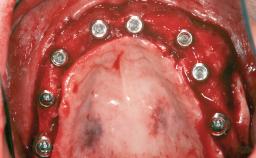

A 45-year-old woman with a completely edentulous maxilla was referred to evaluate the possibility of rehabilitation with an implant-supported prosthesis. This patient was healthy and a non-smoker. She had been wearing a maxillary complete denture opposing a natural mandibular dentition since her twenties. This situation had resulted in progressive resorption of the alveolar ridge, repeatedly creating a need for relining the denture. Twenty years later, despite multiple adaptations and the use of “glues” the denture was unstable and causing the patient psychological and functional discomfort.

# of Implants 8

Type of Implants Reduced-Diameter|Two-Piece

Bone Augmentation Horizontal|Sinus Floor Elevation|Staged|Vertical

Augmentation Materials Autogenous chips|Autogenous block(s)